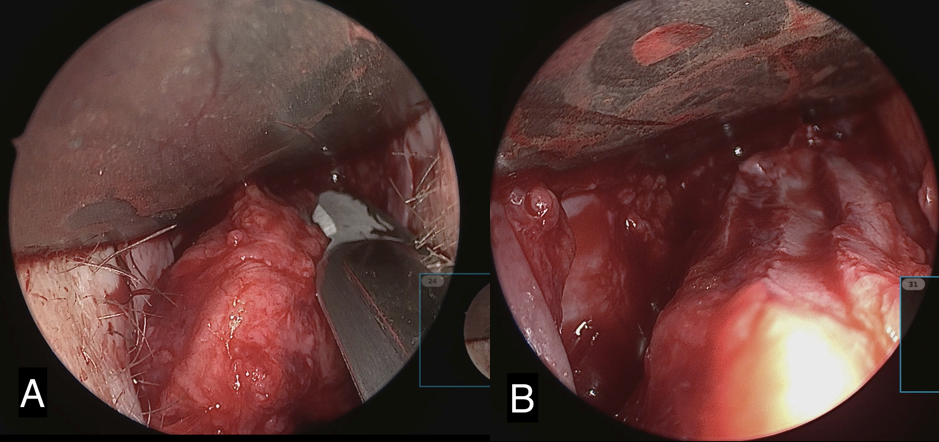

Excellent dorsal exposure is achieved by placing the converse retractor in the nasal cavity on the opposite side of the surgeon, with the flat end of the retractor angled back towards the surgeon. With the #15 blade, the cut is made towards the surgeon with care taken to stay in the same plane across the entire dorsum and not skive towards the skin as you progress with your excision. Successful reduction of the dorsum results in a pocket approximately 2 mm in depth with three parallel structures clearly visualized which are the trimmed edges of the right ULC, dorsal septum, and left ULC (figure 2 and 3).

Next, the butterfly graft is harvested with enough length to span as far laterally on each side as necessary to correct the collapsed nasal valves. See below for description of graft harvesting. The graft is then trimmed at the edges and contoured. The superior edge of the graft is beveled to further reduce the risk of supratip fullness and allow for a smooth nasal dorsal counter (Figure 4). The graft is then placed in the dorsal pocket. If adequate dorsal reduction was achieved, the nasal dorsum should be smooth. Additional re-excision to deepen the dorsal pocket may be required.